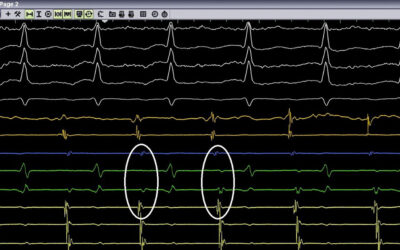

Στο βίντεο μας μιλούν για το νέο Κέντρο Καρδιάς και Αγγείων «Athens Heart Center» στο Ιατρικό Π. Φαλήρου ο κ. Ιωάννης Πυρνοκόκης, Γενικός Διευθυντής και ο δρ Απόστολος Κατσίβας, Καρδιολόγος- Αρρυθμιολόγος, Διευθυντής.